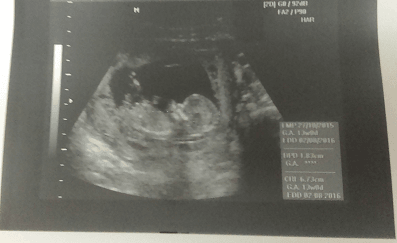

Wczoraj miałam wizytę - wszystko ok, ciąża troszkę większa, bo wszytskie pomiary pokazywały na 12+4, wszystko ok, więc ulga wielka, bardzo długo mi robił usg, mierzył i wszystko ok. Kolejne badania do zrobienia na tokspolazmoze a już sama chciałam sobie robić. Kolejna wizyta za 3 tygodnie. pokazuje zdjęcie z usg, po lewejrączka przy główce, na drugim nóżki i brzuszek![]()

dał mi zdjęcie i mówi :ma Pani swoje nóżki i rączki